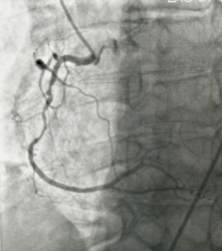

- During the procedure, a thin flexible tube (catheter) is inserted through an artery in the wrist or groin and guided to the heart. A colorless contrast dye is injected, allowing detailed X-ray images to show whether any coronary arteries are narrowed or blocked, and the exact location and severity of the blockage.

- Cardiac catheterization also provides important information about heart muscle function and can assess whether the heart valves are working properly.

- If a significant blockage is found in the coronary arteries, treatment such as balloon angioplasty or stent placement may sometimes be performed during the same procedure.

Angiogram showing detailed images of the coronary arteries and areas of narrowing.